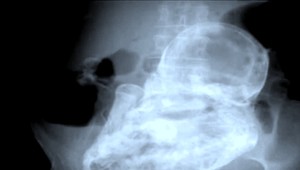

CHICAGO / Istá Američanka doslova zvíťazila nad svojou smrťou. Krátko potom, čo porodila svoje dieťa, jej na 37 sekúnd prestalo biť srdce. V jej prípade totiž nastala popôrodná komplikácia, ktorá sa väčšinou končí smrťou.

Stephanie Arnold z amerického Chicaga svojho synčeka v jednom momente takmer navždy stratila. Krátko potom, čo prišiel na svet, ona skolabovala na operačnom stole. "Moje srdce prestalo pracovať, všetky elektrické signály ukazovali nulu," tvrdí Stephanie.

Jej gynelogička tvrdí, že Stephanie prekonala pri pôrode embóliu plodovou vodou. Komplikácia, ktorú nikto neočakával. Do krvného obehu matky sa dostala plodová voda a zablokovala jej pľúca.